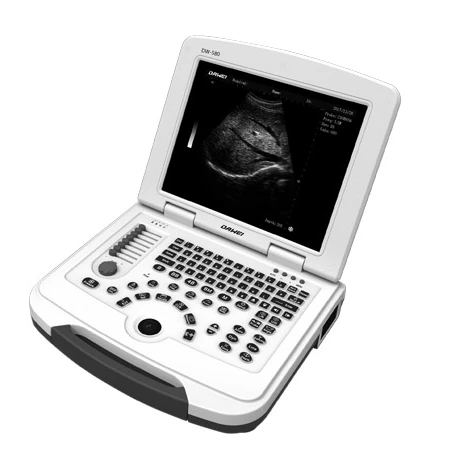

$4,596.00

Medical Ultrasound Instruments Laptop Ultrasound Machine B/W Portable Digital Ultrasound Scanner